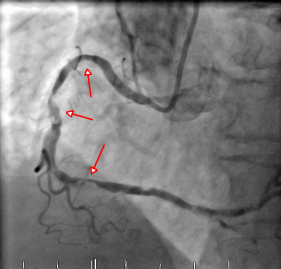

术前示多处狭窄